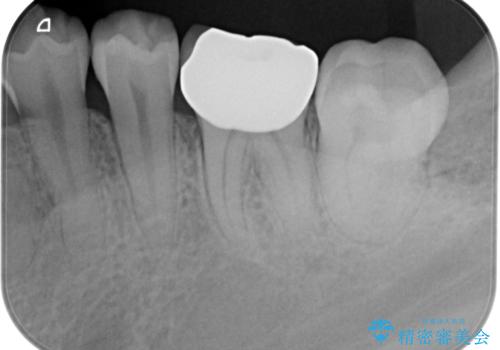

歯冠長延長術をおこなったアプローチの難しい虫歯治療

- 20.9万円(ジルコニアクラウン・仮歯・セラミックインレー)費用は治療当時の料金となります

歯冠長の延長を行ったことで、安定したクラウン治療を行うことができました。